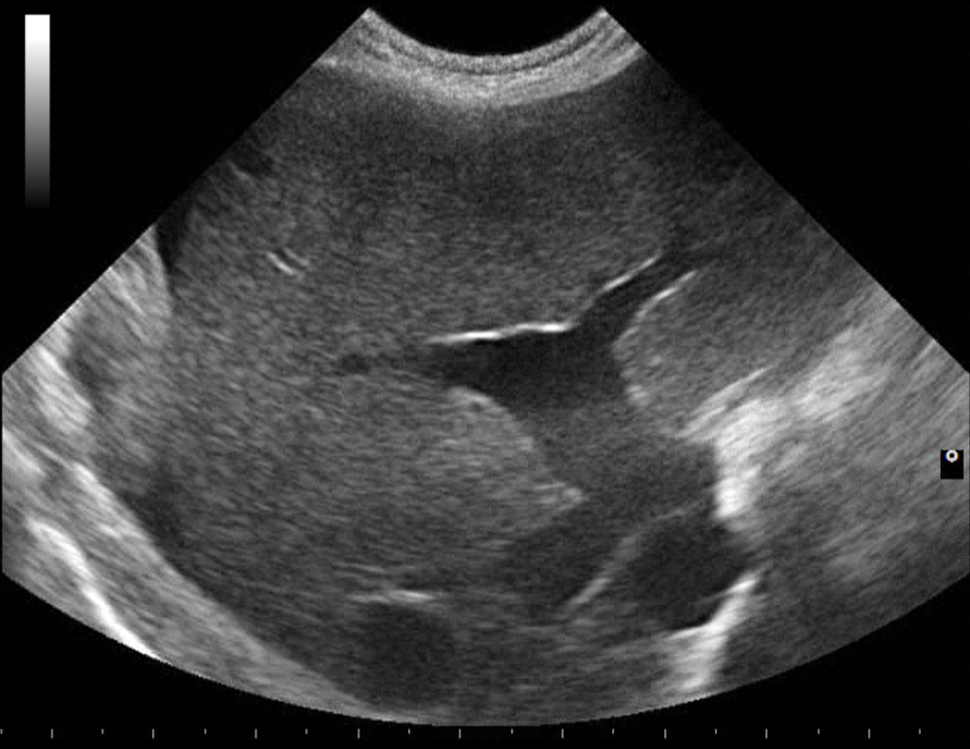

Dutina břišní, mízní uzliny, dutina hrudní, srdce a osrdečník

Praktická sonografie dutiny břišní, hrudní, mízních uzlin a srdce se zaměřením na klinicky významné nálezy.

Jak rozpoznat tekutinu, masy, nodulární změny a srdeční tumory a interpretovat nález v kontextu stavu pacienta.